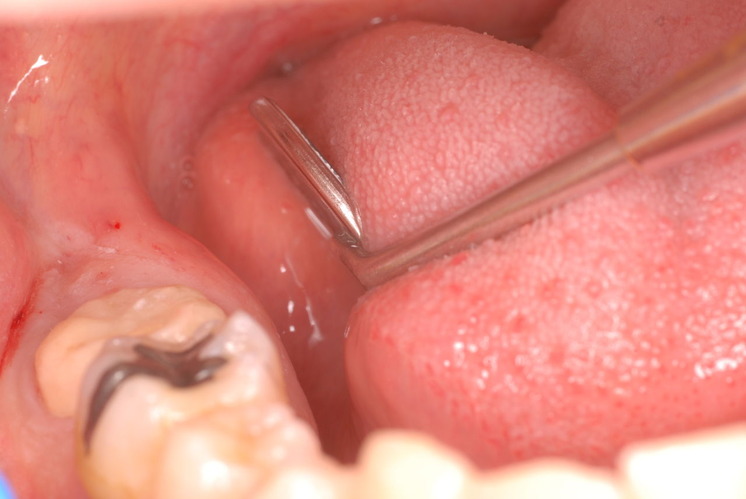

下記は患者に言われるままに血だらけでの不潔な状態で虫歯をとり埋めたようで全然適合していませんし、外れそうになっていました。

外したところです。中は虫歯のオンパレードでした。

適合が悪い銀歯が装着されていて更に虫歯の取残しにより歯髄炎症を起こして神経を取らざるをえなくなりました。神経を除去すれば痛みはなくなります。でもそれは死ぬことなのです。ほぼ寿命は半減したと考えるしかないのです。